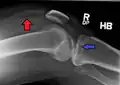

-

Lipohemarthrosis (presence of fat and blood from bone marrow in the joint space after an intraarticular fracture) seen on X-ray in a person with a subtle tibial plateau fracture -

Lipohemarthrosis due to a tibial plateau fracture -

Subtle tibial plateau fracture on an AP X ray of the knee -

A tibial plateau fracture seen on X-ray